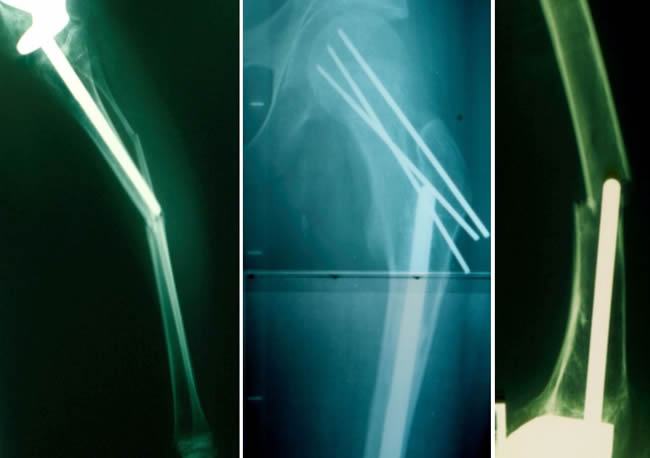

Bifocal Resection

Upper Tibial Ewing's Sarcoma with 3 skip metastases on NMR. Bifocal Resection.

Bipolar Resection

Distal femur expandable prosthesis.

After large lengthening bone stock may become insufficiant

Patient treated for osteosarcoma of proximal tibia when she was 9 years old.

10 years later and after 6 operations the proximal part of femur became too small.

In these cases we advocate to reconstruct the bone defect with an allograft